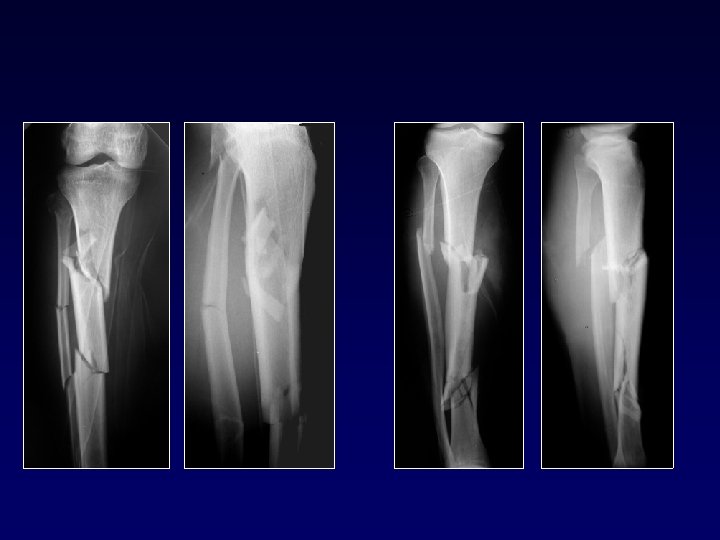

Fratture spiroidi da torsione Tratto di frattura ± lungo - deformazione in rotazione

Fratture spiroidi da torsione La deformazione è importante. I frammenti possono minacciare la pelle

Fratture a due livelli